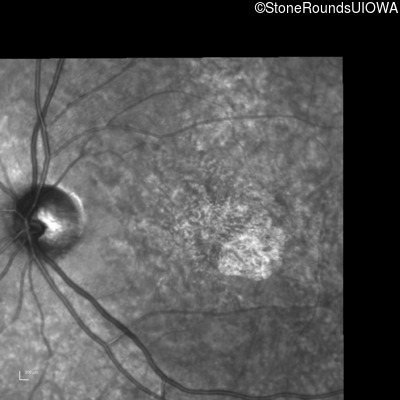

Infrared Fundus Photograph - Right - 20/50 +2

Exemplar